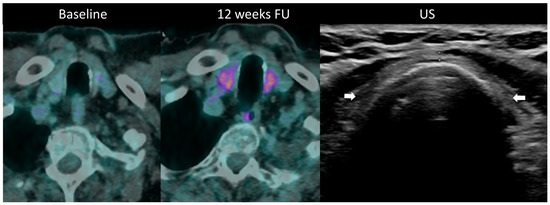

2.5.2. Ir-Thyroiditis

- Park, H.; Hata, A.; Hatabu, H.; Ricciuti, B.; Awad, M.; Nishino, M. Immune-Related Thyroiditis in Patients with Advanced Lung Cancer Treated with Immune Checkpoint Inhibitors: Imaging Features and Clinical Implications. Cancers 2023, 15, 649. [Google Scholar] [CrossRef] [PubMed]